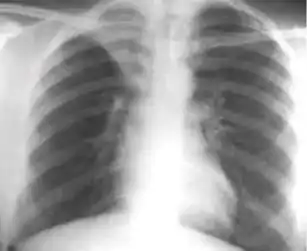

Causes such as bacterial and fungal infections are associated with diffuse abdominal pain, intraperitoneal fluid accumulation, weight loss, fevers, and night sweats. The most common radiographic feature among patients with suspected tuberculous peritonitis was septated compartments of ascitic fluid on ultrasound and abnormal chest X-ray suggestive of previous tuberculosis.[7]

Due to the variety of symptoms experienced by patients with omental caking,[5] omental cakes are most frequently discovered on abdominal computed tomography (CT) or ultrasound. Plain film radiography (X-ray) is not a suggested modality for investigating the spread of cancerous cells in the abdomen due to the poor spatial resolution amongst soft-tissue densities. Contrast resolution obtained through CT allows radiologists to investigate omental caking for morphology, intraperitoneal fluid, and regional lymphadenopathy assists in proper diagnosis so clinicians, surgeons, and oncologists can plan the appropriate course of treatment.[8]